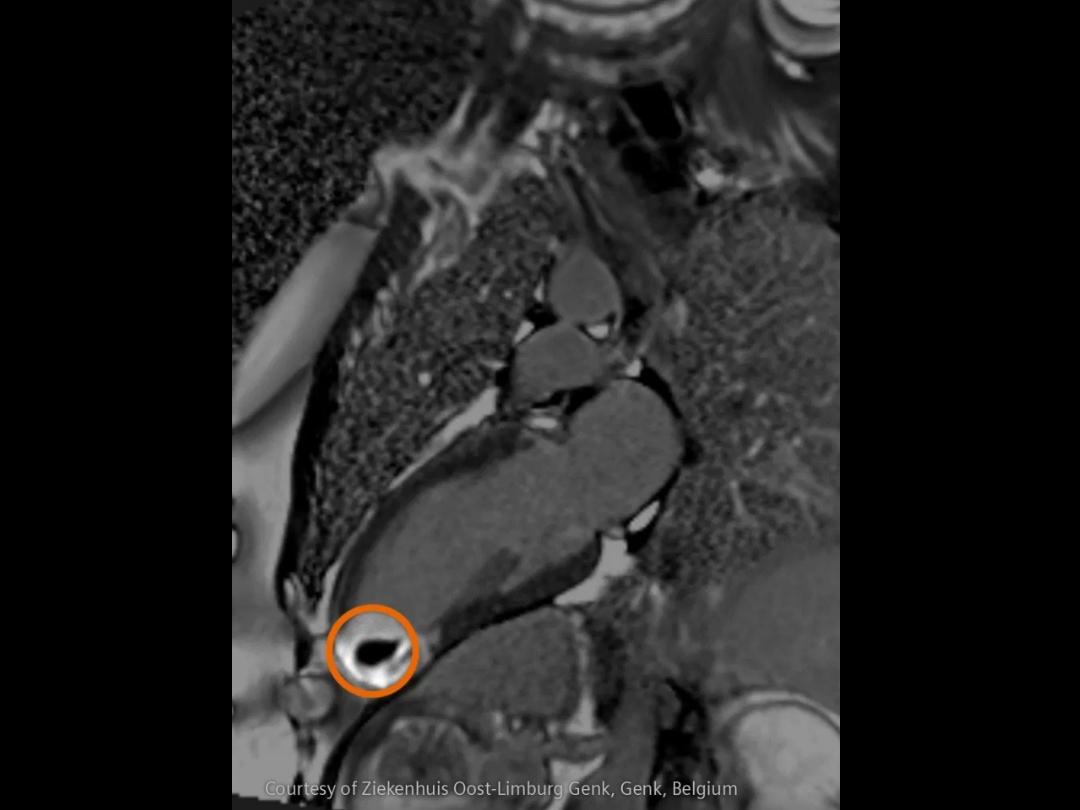

Critical insights in seconds:

How advanced imaging and AI transform stroke workflow

In stroke care, time is brain. Rapid and accurate imaging is crucial to assess the extent of brain injury and guide immediate treatment. Angiography, MRI, CT, ultrasound, and lab diagnostics are essential tools in identifying stroke type, location, and severity. Advances in imaging technology now allow for even faster acquisition, improved resolution, and enhanced visualization of brain tissue and blood vessels. Innovations such as perfusion imaging, real-time vascular mapping, and AI-assisted diagnostics are transforming stroke workflows and enabling precise, timely interventions.